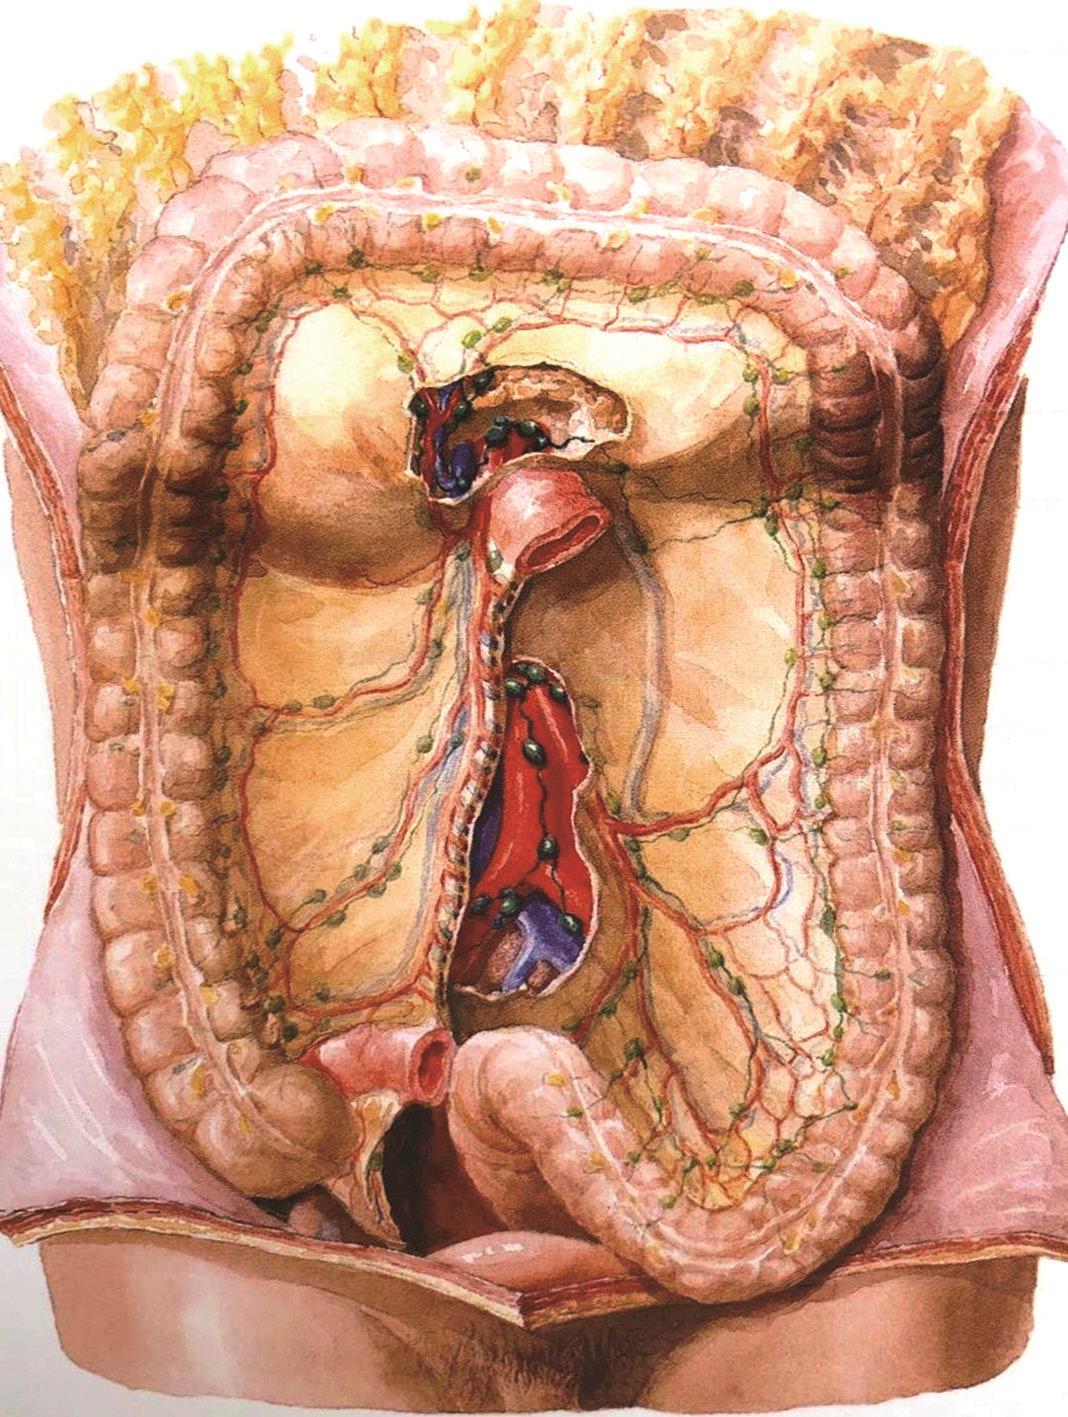

结肠是腹腔内围绕小肠袢的大容量管型结构,是大多数脊椎动物消化系统的重要组成部分,有其鲜明的解剖学特点,包括结肠带、结肠袋和肠脂垂。结肠带明显可见,由肠壁的外纵肌增厚而成,沿结肠纵轴平行排列,3条结肠带均汇聚于阑尾根部,远端在直肠乙状结肠交界处与直肠延续。结肠袋是结肠壁由横沟隔开并向外膨出的囊袋状突起,是由于结肠带比结肠短约1/6而使肠管皱缩而成。肠脂垂是结肠浆膜面沿结肠带两侧分布的脂肪附属物(图2-1)。

图2-1 结肠的特征(结肠带、结肠袋和肠脂垂)及回盲部